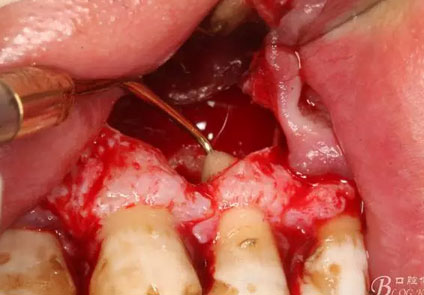

圖16.囊壁摘除后22牙根懸浮在骨腔內(nèi)

圖17.超聲骨刀根尖切除+倒預(yù)備根管